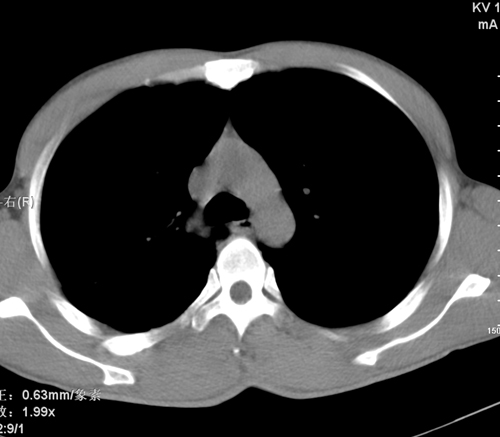

标题: CT24548:男 31 咳嗽 咯血一天 行CT检查 [打印本页]

标题: CT24548:男 31 咳嗽 咯血一天 行CT检查

ct考虑结核 但化验结果示白细胞总数 淋巴均正常,血沉7mm/h不快,请看看结核 支扩还是其他

右肺上叶尖端,后段下叶背段结核伴空洞形成

继发性肺结核伴空洞形成!

右肺继发性肺结核伴空洞形成!

考虑右肺继发性肺结核伴空洞形成。